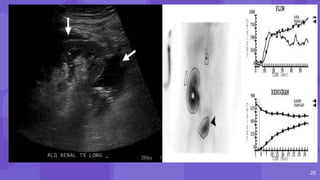

Post Biopsy Renal AVF and Pseudoaneurysm

● AVF Pseudoaneurysm

AVFs have a feeding

artery with a high-

velocity low-resistance

waveform at spectral

analysis

● narrow neck

● to-and-fro pattern of

blood flow

● yin-yang sign

14 Post Biopsy RenalAVF and Pseudoaneurysm ● AVF may form when an artery and vein are lacerated, whereas PA results when only the artery is lacerated ● AVF Pseudoaneurysm AVFs have a feeding artery with a high- velocity low-resistance waveform at spectral analysis ● narrow neck ● to-and-fro pattern of blood flow ● yin-yang sign

• #16 Postbiopsy pseudoaneurysm and arteriovenous fistula (AVF) Color Doppler image shows a round area of bidirectional flow (arrow) in the upper transplant kidney, consistent with a pseudoaneurysm. Spectral analysis at a site of focal aliasing near the pseudoaneurysm shows high-velocity systolic flow and low-resistance diastolic flow, characteristic features of an AVF Three-dimensional volume-rendered image shows the renal artery (white arrow) with an early draining vein (black arrow) as well as the pseudoaneurysm (arrowhead).